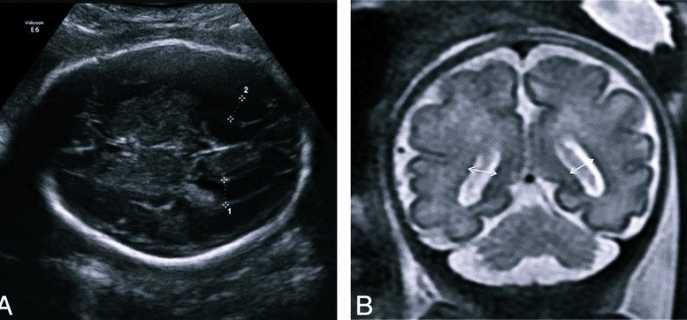

Анализ структур головного мозга у плода проводят во втором триместре, в период между 18 и 27 неделями беременности. В большинстве случаев патологические изменения обнаруживаются на плановом УЗИ. Диагноз также ставят на 30-33 недели беременности.

Показатели УЗИ, МРТ, проведенных до родов и после, в 57-83% случаев существенно отличаются. Если у плода обнаружили расширение желудочков, не стоит паниковать. Для подтверждения или опровержения диагноза необходимо пройти повторное ультразвуковое и томографическое обследование новорожденного. Такие доводы представлены в издании «Частота и причины расхождений диагностических изображений у детей с вентрикуломегалией» G. M. Senapati, 2010.